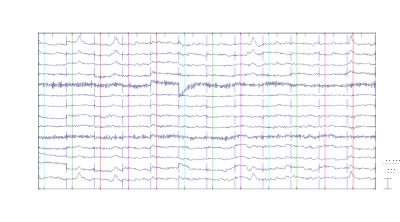

EEG chart.

Diagnostic Doctor EEG Electroencephalogram Health Heart Measure Medical Medicine